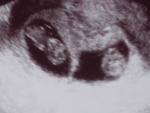

Klik hier om een link te hebben waarmee u dit artikel later terug kunt lezen.Wat!! TWEE ?

Klik op de afbeelding om de link te volgen Onze eerste echo staat op onze agenda, "Dinsdag 12 juni '06 om 8 uur ziekenhuis Hasseltsestraat." (met twee cirkels rond)  Ter plaatse, inschrijven aan de balie, in de wachtzaal, trappel trappel ... Ik ga met een gerust gemoed binnen, sta vol zelfvertrouwen naast de marteltafel en kijk naar het zwartwit schermpje.  In mijn hoofd houd in mij voor ogen : een zwarte vlek met daarin een silhoutte van een foetus. Ik weet dat ik direct op zoek moet gaan naar een kloppend hartje.  Dat is belangrijk. Al vlug komen de eerste beelden binnen,  één zwarte vlek, twee zwarte vlekken en een simpel zinnetje volgt :" Het zijn er twee....". Even wordt het stil, ik sta aan de grond genageld, mijn rug wil niet meer bewegen en mijn bloed trekt naar mijn hersenen.  Die hadden dringend extra bloed nodig want in drie seconden hebben die voor mij berekend dat niets nog zou zijn zoals het was.  Ons geluk : dubbel zo groot, ons budget gehalveerd, onze nachtrust nihil, ons huis te klein, onze auto..... WATTE ik met een bus gaan rondrijden !!   Mijn hart bleef bijna stil staan.  Ondertussen waren Claire en de "Kinkologe" al een stuk verder in de onderzoeken, ik probeerde terug aan te pikken maar mijn functioneren was ontregeld.  Dat zou zo nog blijven tot laat die avond.

Sandy

Twee nachten heb ik nachtmerries gehad ...verdorie een tweeling.  En wat als ik ze niet uit elkaar kan houden?? En als ik altijd dezelfde eten geef.  Oei, oei, niet meer slapen. En Sandy heeft de hele dag bleek gezien. We zijn dolgelukkig maar het lijkt alsof we nu meer zorgen om onze zwangerschap gaan hebben.

Claire - 6 weken en 4 dagen